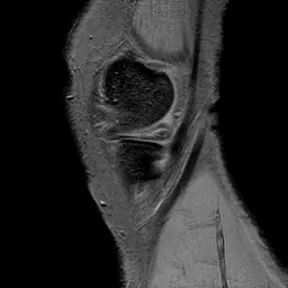

半月板放射状撕裂

1、半月板体部的撕裂在矢状面上表现为蝶形的半月板内出现与长轴垂直的线状高信号2、前后角的放射状撕裂因与矢状面平行而表现为III级高信号3、好发于半月板的内侧1/34、外侧半月板多见